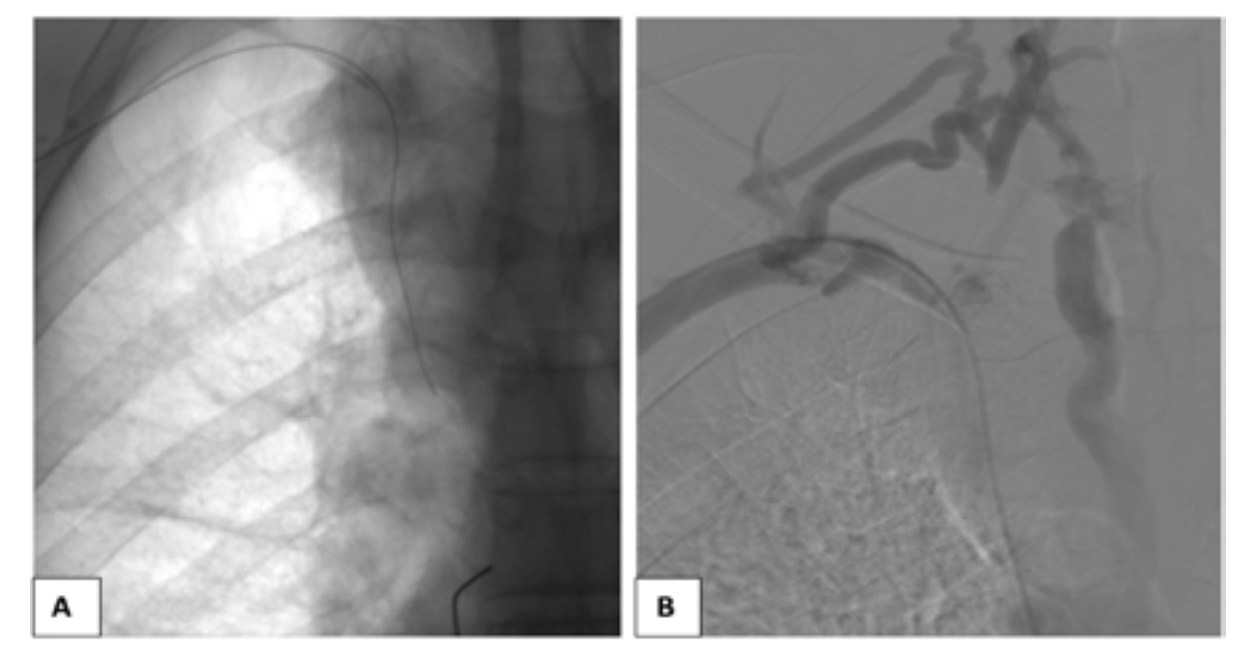

The venacavogram confirmed the absence of thrombus and revealed a stenosis in 3 cases and an occlusion in 2 cases. The stenosis/occlusion localization was the SVC in 3 cases and both SVC and the innominate venous trunk (IVT) in 2 cases.

From a therapeutic point of view, endovascular treatment of SVCS had been performed under local anesthesia. Percutaneous vena femoral approach was carried out in 2 cases. Three patients also required the use of the basilica pathway. Before stenting, the caval stenosis was dilated two or three times for almost 10 minutes by means of balloon inflation to the estimated diameter in three cases. We also routinely performed post-stent dilatation. In all procedures, a self-expanding stent had been deployed. The details regarding the stent deployed are summarized in Table 1. As an immediate follow-up, the patients experienced a quick relief of symptoms between 48-72 hours.